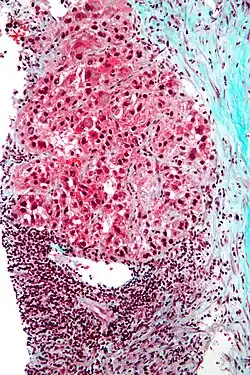

Mallory bodies in hepatocellular carcinoma. Trichrome stain.